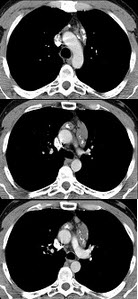

男性患者,19岁,咳嗽、发热1周,X线检查如图,最可能的诊断是( )

A:左下肺不张

B:左侧胸膜肥厚

C:左下肺炎症

D:左侧胸腔积液

E:左下支气管扩张